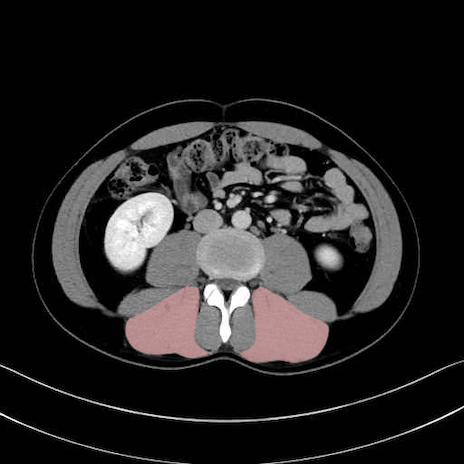

脊柱起立筋 (Erector spinae)

多裂筋 (Multifidus)

2. 腸腰筋群と骨盤底筋

大腰筋 (Psoas major)

腸骨筋 (Iliacus)